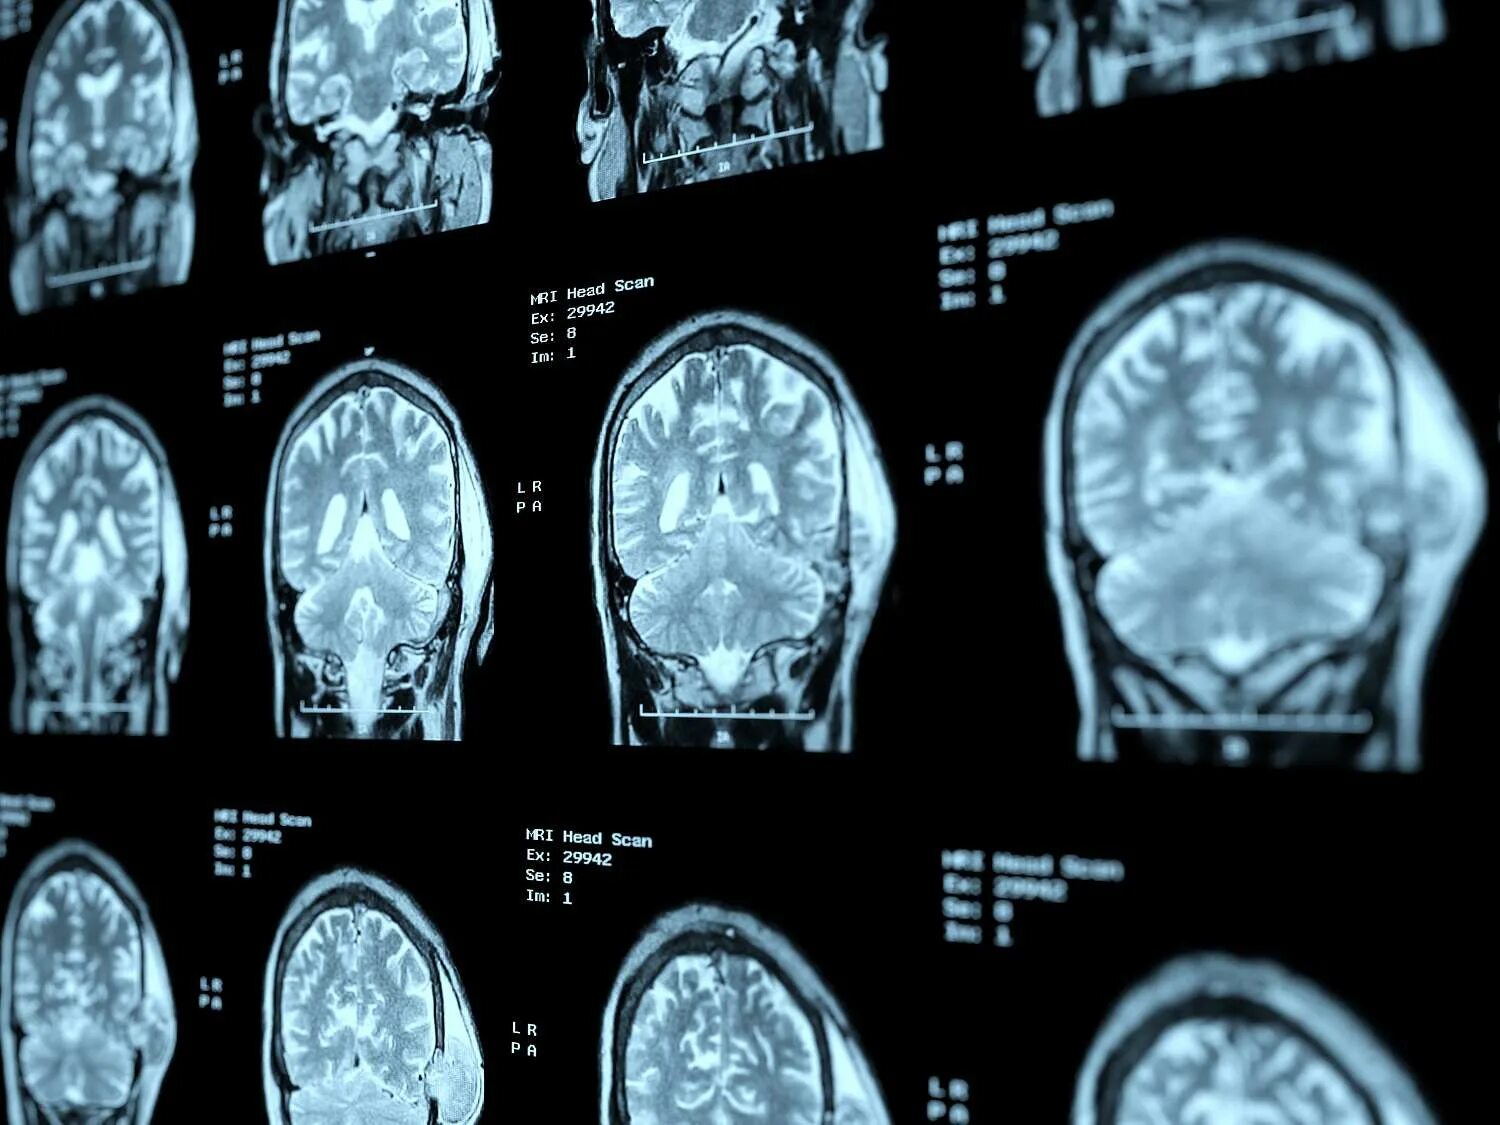

Просмотр снимков мрт